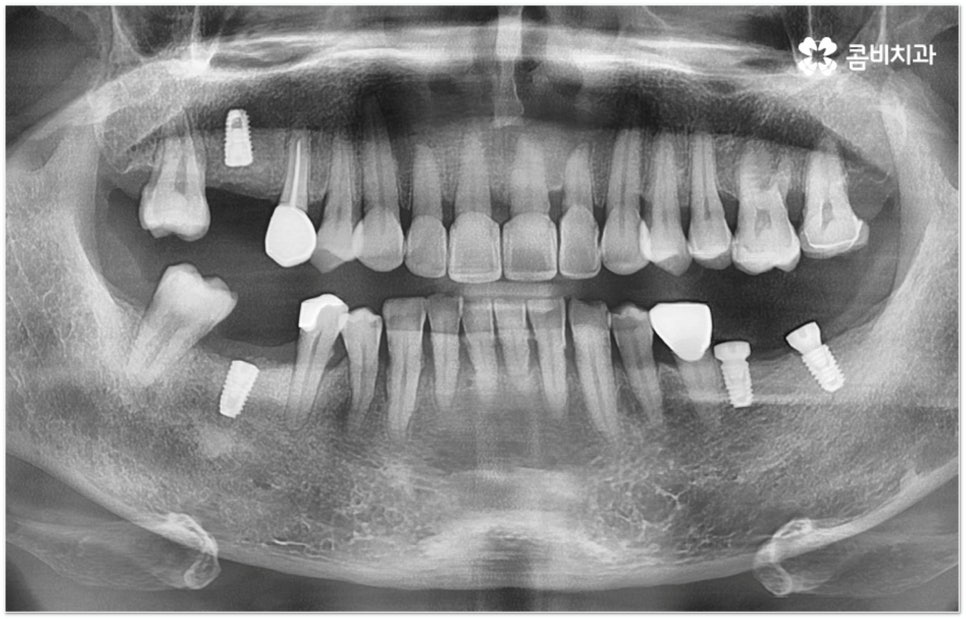

그러나 임플란트는 잇몸뼈에 직접 심어서 고정시키는 방식인 만큼 만약 환자분의 잇몸뼈가 부족하거나 치아가 빠진 후 오랜 시간이 지나 이미 잇몸뼈 소실이 상당 부분 이루어진 상태라고 한다면 먼저 골이식을 통해 이를 보충한 후 식립을 진행하는 뼈이식임플란트 방식을 이용할 필요가 있어요. 골이식 과정은 바탕이 되는 잇몸뼈의 밀도나 높이, 두께가 부족한 부분에 이식 재료를 심어주어 뼈를 재건해 주는 것인데 충분한 시간을 두고 무리하지 않게 진행하는 것이 뼈이식임플란트 수술의 성공률 및 안정적인 지속성을 높일 수 있는 방법이 될 거예요.

뼈이식임플란트 가 필요한지 살펴볼 때 3D CT 촬영과 같은 정밀 진단을 통해서 환자분의 잇몸뼈 두께 등 치조골 상태 뿐 만 아니라 구강 구조, 치아 및 잇몸 상태, 신경관 위치, 상악동까지의 거리 등을 꼼꼼하게 확인하여 치료 계획을 세우고 필요하다면 구강 질환에 대한 치료나 상악동 거상술 등을 선행하며 잇몸뼈 부족에 대해서도 골이식 과정을 먼저 진행하게 되는데요, 이러한 뼈이식임플란트 시술은 상당히 고난도의 복잡한 치과 진료인 만큼 관련 임상 경험이 풍부한 의료진과 함께 하는 것이 굉장히 중요하며 또한 수술 후 관리 면에서도 더욱 신경을 써 주시길 당부드리고 있어요.

또한 전신질환을 앓고 있는 분들이 치아를 잃게 되신 경우 임플란트 수술 가능 여부에 대해 걱정하실 수 있는데 관련 기술과 방법들이 꾸준히 발달해 온 만큼 너무 겁을 먹기 보다는 꼼꼼한 검진 및 면밀한 상담을 통해 치아 상실의 불편함을 대체할 수 있는 방법을 적극적으로 찾아보시는 게 도움이 될 수 있어요. 특히 오랜 기간 상용해 오신 약이 있다면 이로 인해 임플란트 수술의 성공 가능성 내지 예후에 크게 영향을 줄 수 있기 때문에 담당 의료진과 충분히 사전 상담을 하는 것이 중요하다는 점은 분명하나 이로 인해 무조건 임플란트가 불가능하다고 생각하시고 지레 포기하시기 보다는 신경써서 주의할 점이 있다는 쪽으로 생각하시면 좋을 거예요.

대표적으로 고혈압, 당뇨를 가지고 계신 분들을 예로 들어보면 지혈에 문제가 생기거나 감염에 취약할 수 있으므로 의료진과의 지속적인 소통을 통해 약 복용 계획을 수술 일정과 조율하면서 정밀 검진을 통해 혹시 모를 부작용들을 미연에 방지하고 사후까지 꼼꼼하게 케어할 수 있는 치과에서 임플란트 수술을 받으시길 권유드리고 있습니다.